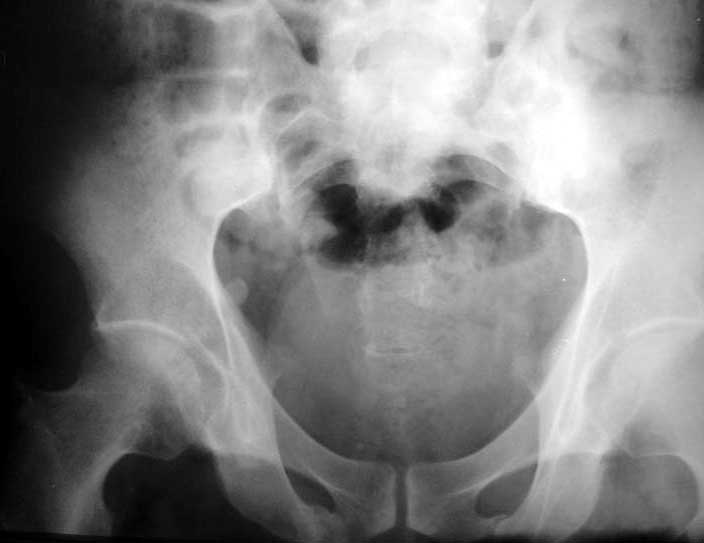

Больной 64 лет, работник тяжелого физического труда, 29.10.02 на производстве получил удар трубой по переднему отделу таза. 2 месяца постельного режима, с 4 месяцев ходит с тростью. Беспокоят тянущие боли в нижних конечнстях при нагрузке, периодически ночные боли, хромота, постоянно припимает анальгетики. Снимки прилагаются. Виден подвывих в правом крестцово-подвздошном сочленении. Как лучше помочь пациенту? Заранее спасибо.